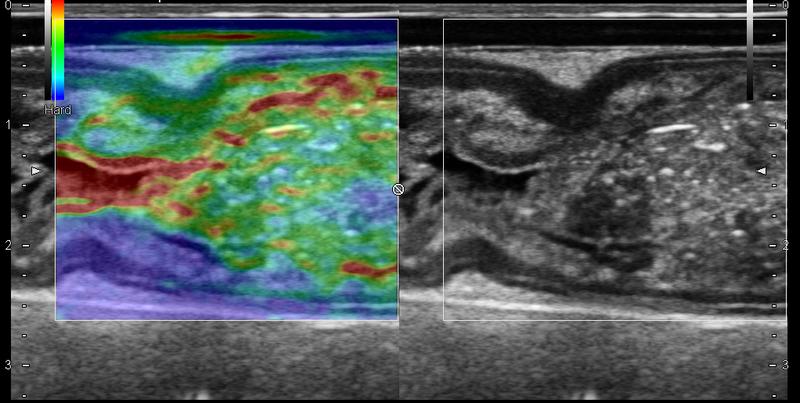

Elastografie verbessert Therapie bei Morbus Crohn

Bei Morbus Crohn Patienten kann verändertes Darmgewebe durch eine innovative Methode, die Elastografie, verlässlich diagnostiziert werden. Dies zeigen…

Ultraschall statt Stich in die Leber: Elastografie ersetzt Gewebeproben

Eine Million Menschen in Deutschland leiden an einer Lebererkrankung wie Fettleber oder Hepatitis. Ohne Behandlung droht ihnen eine Leberzirrhose oder -krebs….